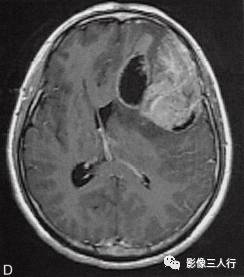

左侧额颞叶多形性胶质母细胞瘤

A.T1WI横断面;B.T2WI横断面;CFLAIR横断面;D.T1WI增强;E.T1WI增强冠状面;F.T1WI增强矢状面;G.HE×40;H.GFAR( )×40

左侧额颞叶见较大不规则囊实性肿块,大小约5.4cm×8.3cm,平扫T1WI呈低信号、T2WI呈高信号(图A、B),肿块内有斑片状囊变区;增强扫描肿块实性部分呈不均匀明显强化,囊性部分呈环形强化(图D~F)。肿块占位效应明显,周围见环形水肿(图C)。